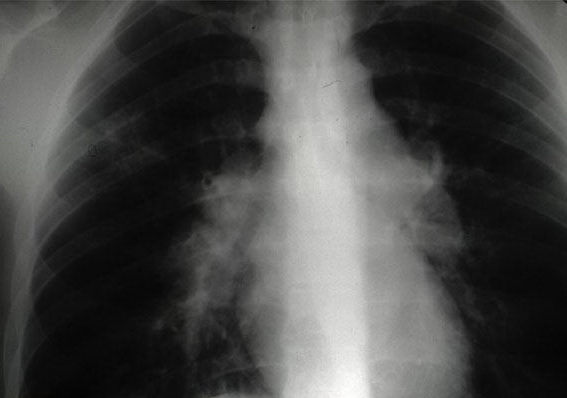

Sarcoidosis = الساركوئيد